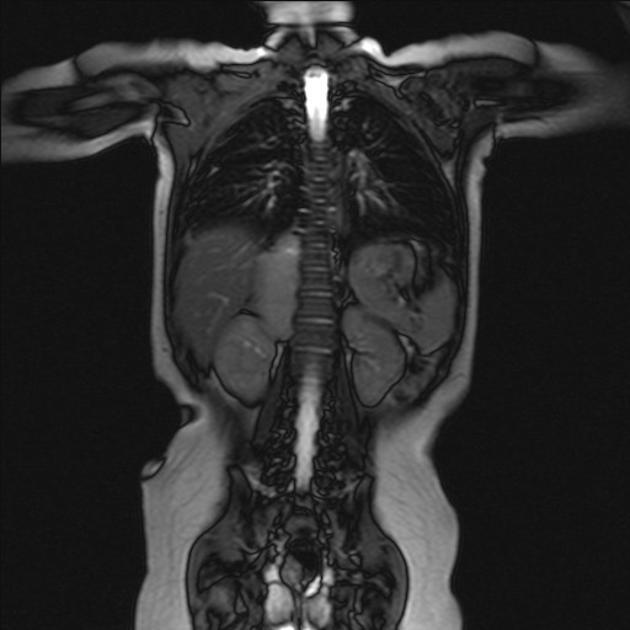

Main differences between Wilms and Neuroblastoma

Calcifications and metastasis to bones in neuroblastoma

Invasion of vessels and well defined in Wilms (neuro encases and is irreguar)

4 years in Wilms and 2 years in Neuro